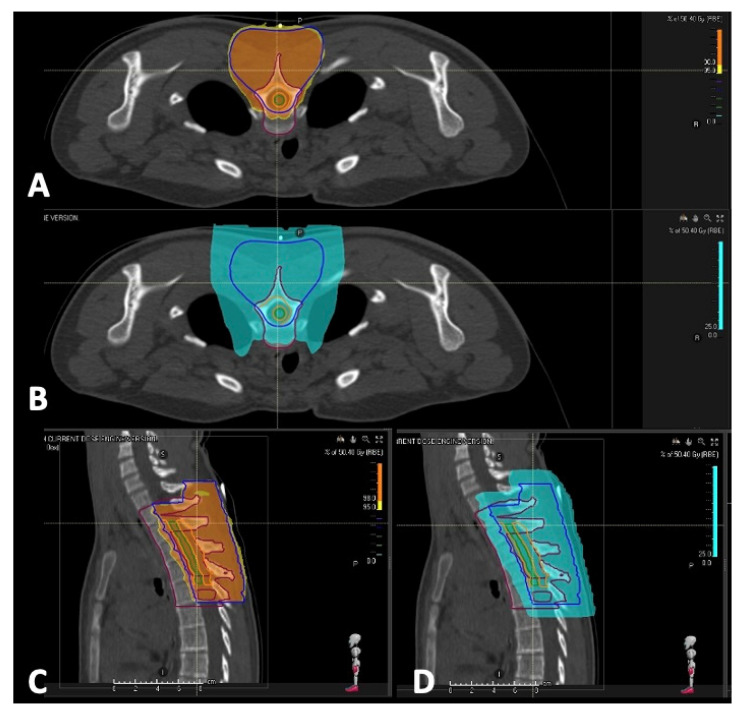

背景:脊柱孤立性纤维性肿瘤(SFTs)是一种罕见的肿瘤实体,在儿科人群中几乎是轶事。他们有很高的复发率,代表了一个持续的肿瘤挑战。方法:在这篇文章中,我们从一个病例报告开始进行了系统的回顾,以强调目前在治疗这些肿瘤方面的最新进展。结果:脊髓孤立性纤维性肿瘤(SFTs)是一种罕见的生长缓慢的肿瘤,可发生在髓内或髓外。只有有限数量的研究关注于原发性小儿脊髓定位。文献记载了5例小儿脊柱SFT病例。在MRI上,它们通常表现为高度血管化,对比度增强的肿块。组织学上,它们由胶原基质中的梭形细胞组成,具有鹿角状血管。更具侵袭性的亚型,如去分化SFTs,类似于高级别肉瘤。NAB2-STAT6融合是驱动EGFR信号、胶原生成和纤维化的关键标志物。其他诊断标志物包括CD34、CD99和Bcl-2。手术切除仍是主要治疗方法。在转移性病例中,化疗-主要是蒽环类药物,达卡巴嗪或替莫唑胺-被采用,尽管没有标准化的儿科方案存在。抗血管生成药物,包括酪氨酸激酶抑制剂,已经显示出前景。放疗用于术后局部疾病控制,但其对生存的影响仍在调查中。结论:手术仍然是治疗的基石,对疾病的自然病程和症状控制有重要影响。虽然在成人中探索放疗和化疗的临床试验正在进行中,但尚未为儿科患者建立特定的治疗方案。

Background: Spinal solitary fibrous tumors (SFTs) are a rare oncological entity, almost anecdotal in the pediatric population. They have a high relapse rate and represent an ongoing oncological challenge. Methods: In this article, we conducted a systematic review starting from a case report to highlight the current state of the art in managing these tumors. Results: Spinal solitary fibrous tumors (SFTs) are rare, slow-growing neoplasms that can be either intra- or extramedullary. Only a limited number of studies focus on primary pediatric spinal cord localization. Five pediatric cases of spinal SFT have been documented in the literature. On MRI, they typically present as highly vascularized, contrast-enhancing masses. Histologically, they are composed of spindle-shaped cells within a collagenous stroma featuring staghorn-shaped blood vessels. More aggressive subtypes, such as dedifferentiated SFTs, resemble high-grade sarcomas. The NAB2-STAT6 fusion is a key marker, driving EGFR signaling, collagen production, and fibrosis. Additional diagnostic markers include CD34, CD99, and Bcl-2. Surgical resection remains the primary treatment. In metastatic cases, chemotherapy-mainly with anthracyclines, dacarbazine, or temozolomide-is employed, although no standardized pediatric protocols exist. Anti-angiogenic agents, including tyrosine kinase inhibitors, have shown promise. Radiotherapy is used postoperatively for local disease control, but its impact on survival is still under investigation. Conclusions: Surgery remains the cornerstone of treatment, significantly impacting the natural history of the disease and symptom control. While clinical trials exploring radiotherapy and chemotherapy are ongoing in adults, no specific treatment protocol has been established for pediatric patients.